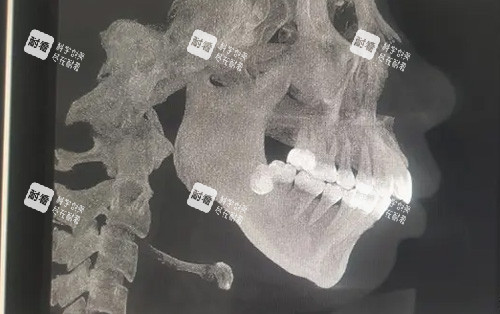

在进行正畸正颌联合治疗之前,患者需要进行超全的检查和评估。这包括口腔检查,医生会检查牙齿的排列、咬合关系、口腔卫生状况等;影像学检查,如X光片、CT扫描等,这些检查可以清晰地显示颌骨的形态、结构和位置,帮助医生比较准判断骨性嘴凸的程度和类型;模型分析,医生会取患者的牙齿模型,通过对模型的分析进一步了解牙齿和颌骨的情况。此外,医生还会与患者进行充分的沟通,了解患者的治疗期望和需求,综合各方面的信息制定个性化的治疗方案。